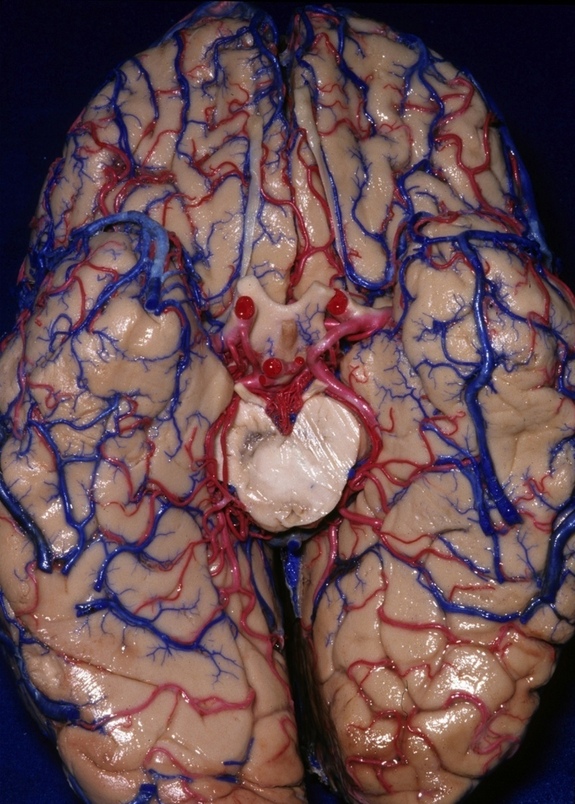

Estas imágenes son parte de una colección de anatomía del cerebro humano hechas por el Dr. Albert Rhoton (November 18, 1932 – February 21, 2016) un neurocirujano y profesor de la Universidad de Florida, las imágenes permiten a los cirujanos ver las estructuras cerebrales delicadas en ángulos precisos.

Con tintes azules y rojos brillantes los vasos sanguíneos son visibles con mayor facilidad, por lo que los cirujanos pueden planificar mejor los enfoques quirúrgicos delicados. Explora la geografía del cerebro humano a través de esta colección de imágenes del Dr. Rhoton disponibles en iTunes.

Mirando lateralmente, esta imagen muestra al hemisferio cerebral derecho. A pesar de las afirmaciones hechas por la psicología popular, el hemisferio derecho no es especialmente creativo, ni el cerebro izquierdo inherentemente más lógico. Un dato curioso es que la información sensorial de cada lado del cuerpo, viaja al lado opuesto del cerebro.